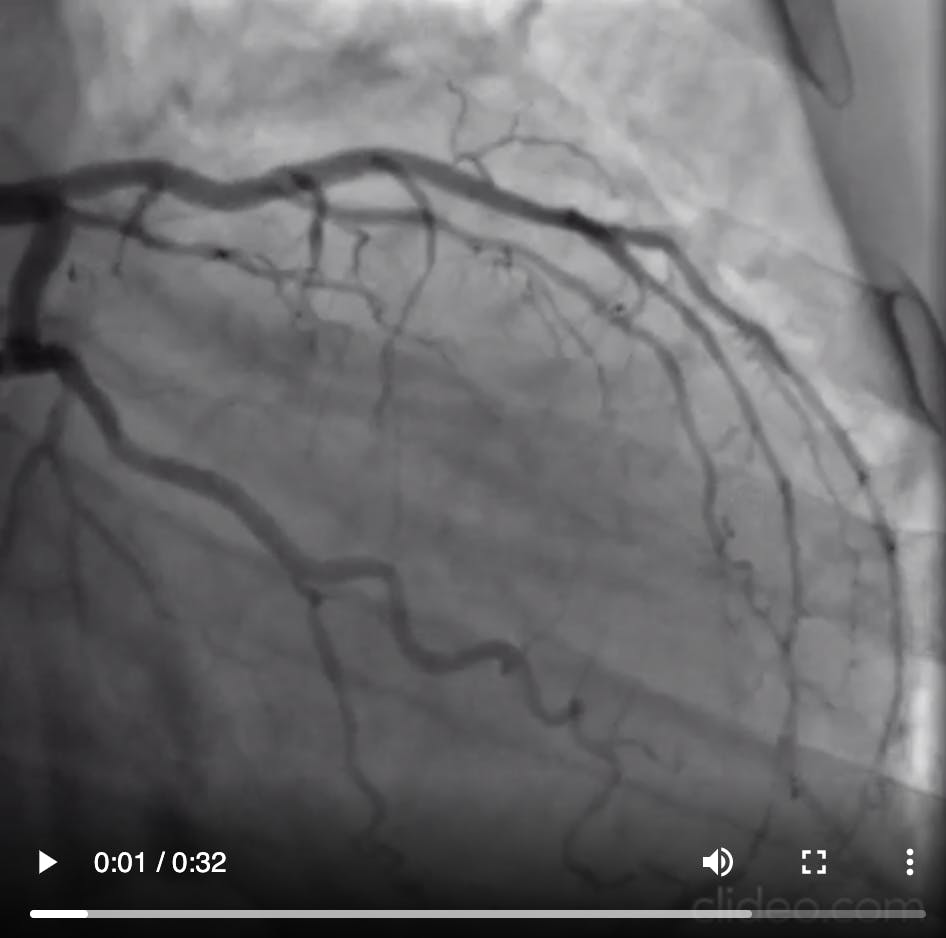

Click the images to watch videos of the block and deliver technique.